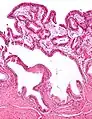

En medicina, la colesterolosis vesicular es la acumulación focal de histiocitos espumosos (macrófagos) cargados de colesterol en la lámina propia de la vesícula biliar.[1]

![]() Microfotografía de colesterolosis vesicular. H&E stain. | ||

A veces se llama vesícula biliar de fresa por el aspecto punteado de la superficie de la mucosa en un examen general, similar al que presentan las fresas. La colesterolosis está causada por una acumulación anormal de depósitos de ésteres de colesterol en macrófagos dentro de la lámina propia (células espumosas) y en el epitelio de la mucosa. La vesícula biliar puede estar afectada de forma localizada o de forma difusa. La forma difusa se presenta macroscópicamente como una mucosa roja brillante con motas amarillas (debido a los lípidos), de ahí la comparación con la fresa. No está ligada a la colelitiasis (cálculos vesiculares) ni a la colecistitis (inflamación de la vesícula biliar).[2]